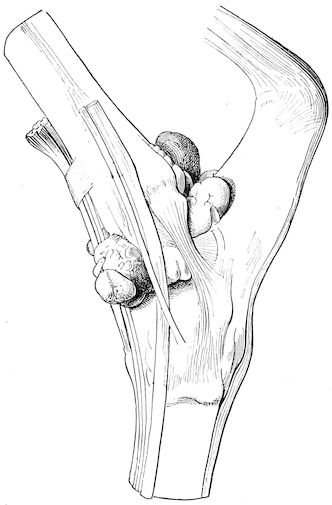

At the end of this second phase, swellings appear, due to synovitis or arthritis of the extremities, synovitis of the sesamoid or navicular sheaths or to inter-phalangeal arthritis or arthritis of the fetlock joint. Weakness becomes marked, and the appetite is very irregular.

Fig. 3.—Pig suffering from osseous cachexia (fourth stage).

Such shocks would be of no importance to a healthy animal, but to one suffering from osseous cachexia, any violence, or even the slightest muscular effort may be followed by fracture of the gravest character, involving even the vertebral column. In cows the pelvis, femur, and tibia are most frequently injured.

In horses, particularly in riding horses, fractures are commonest in the region of the forearm, cannon bone, and anterior phalanges. So extremely fragile are the bones at this stage that the horse represented herewith broke twelve ribs at one time by simply falling on its side. It is interesting to note that such fractures are never accompanied by any extensive bleeding. They have little tendency to repair, no real callus formation occurs, and on post-mortem examination one often finds the ends unconnected by temporary callus, worn, and rounded by reciprocal friction.

At this stage but under other circumstances, the animals show great reluctance to rise, remaining down for twelve to twenty-four hours without shifting their position. If forced to get up, they stand as though fixed in one position, the respiration and circulation become rapid, and they soon grow tired and fall.

114. The fourth phase, or period of osteomalacia, i.e. softening of the bones, is also the last. It is rarely seen in large animals like horses and oxen, because accidents so often accompany the preceding stages and necessitate slaughter; but it is common in goats and pigs.

In this phase the bones become elastic, soft and depressible, yielding to the pressure of the operator’s fingers.

Fig. 4.—Deformity of the face in the horse shown in Fig. 2.

The flat bones are particularly liable to this change, which is common to domesticated animals. The bones of the head are the first to suffer; later those of the pelvis. The lower jaw becomes swollen, particularly about the centre of the branches which may attain three, four, or five times, their normal thickness.

The depression in the submaxillary space disappears. The upper jaw undergoes similar changes, becoming deformed and thickened until the cavities of the sinuses and the hollow appearance of the palate are lost, while the face is so changed that it cannot be recognised as that of a horse, goat, etc.

The molar teeth are almost buried, their tables alone being visible at the bottom of a depression, the edges of which rise above the neighbouring parts (pig).

Mastication is clearly impossible, the jaws appear paralysed, the muscles powerless, and only swallowing is possible, a fact which explains why life is only prolonged to this stage in animals which can be fed with a spoon or bottle (pigs and goats). The bones of the cranium, although greatly changed in texture, are always less deformed than those of the face.

The changes are such that it is often easy with a mere post-mortem knife to cut the head completely in two. Osseous tissue, properly so-called, has disappeared.

All the constituent tissues, with the exception of the skin and muscles, i.e., the bone, periosteum and aponeuroses, have the appearance and consistence on section of the fibro-lardaceous tissue seen in chronic inflammation.

Fig. 5.—Head of a pig suffering from osseous cachexia.

Fig. 6.—Osseous cachexia. This condition developed in two months, the last month of gestation and the first of lactation.

Fig. 7.—Osseous cachexia: softening of the maxillæ.

Fig. 8.—Transverse section through the middle region of the face in a pig suffering from osseous cachexia.

18In the final stages, the bones may be cut with a knife, and a time arrives when bony tissue seems completely to have disappeared; thus, as shown in Fig. 8 herewith, it was possible to cut the entire head of a pig into thin slices without the slightest difficulty. All parts of the head had been affected by the softening change.